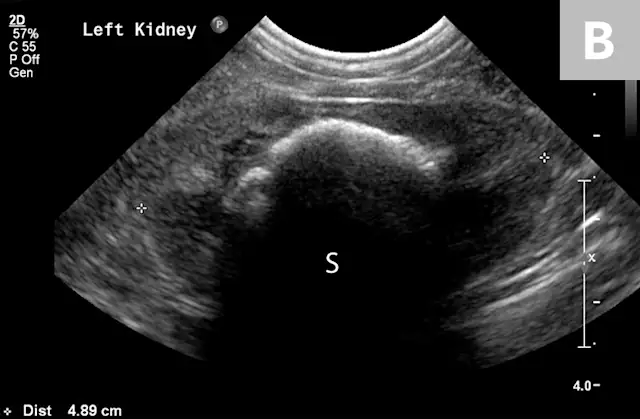

FIGURE 6A

Mild to moderate right hydronephrosis and proximal ureteral dilation in a Dalmatian.

Clinical signs associated with ureteral calculi may range from chronic non-specific signs to acute or chronic renal failure. The presence of hydronephrosis can be highly suggestive of a ureteral obstruction (Figure 6).